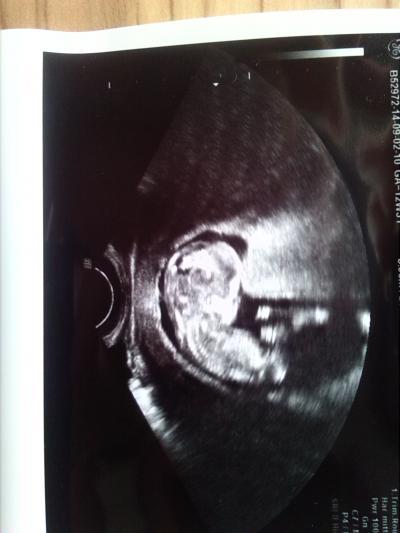

Und alles supi .Es ist ca ne woche grösser aber der Termin bleibt erstmal.morgen hab ich dann Nackenfaltenmessen .und heute mal noch ein schönes Bild

Bild zu wieder da ..... - Forum für März - Mamis

Na, das klingt doch gut. Schönes Foto!

Total süßes Bild , toll das alles gut ist

Ui so ein tolles Foto und die Daumen für die Nackenfaltenmessung sind gedrückt